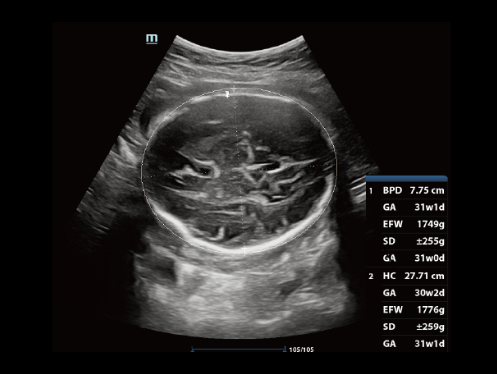

W aparacie DC-80A X-Insight zintegrowano inteligentne rozwi?zania z profesjonalnymi narz?dziami diagnostycznymi w ró?nych aplikacjach i podczas ca?ego cyklu badań: od pocz?tku ci??y, poprzez badania prenatalne, a? po opiek? poporodow?.

Obrazy kliniczne